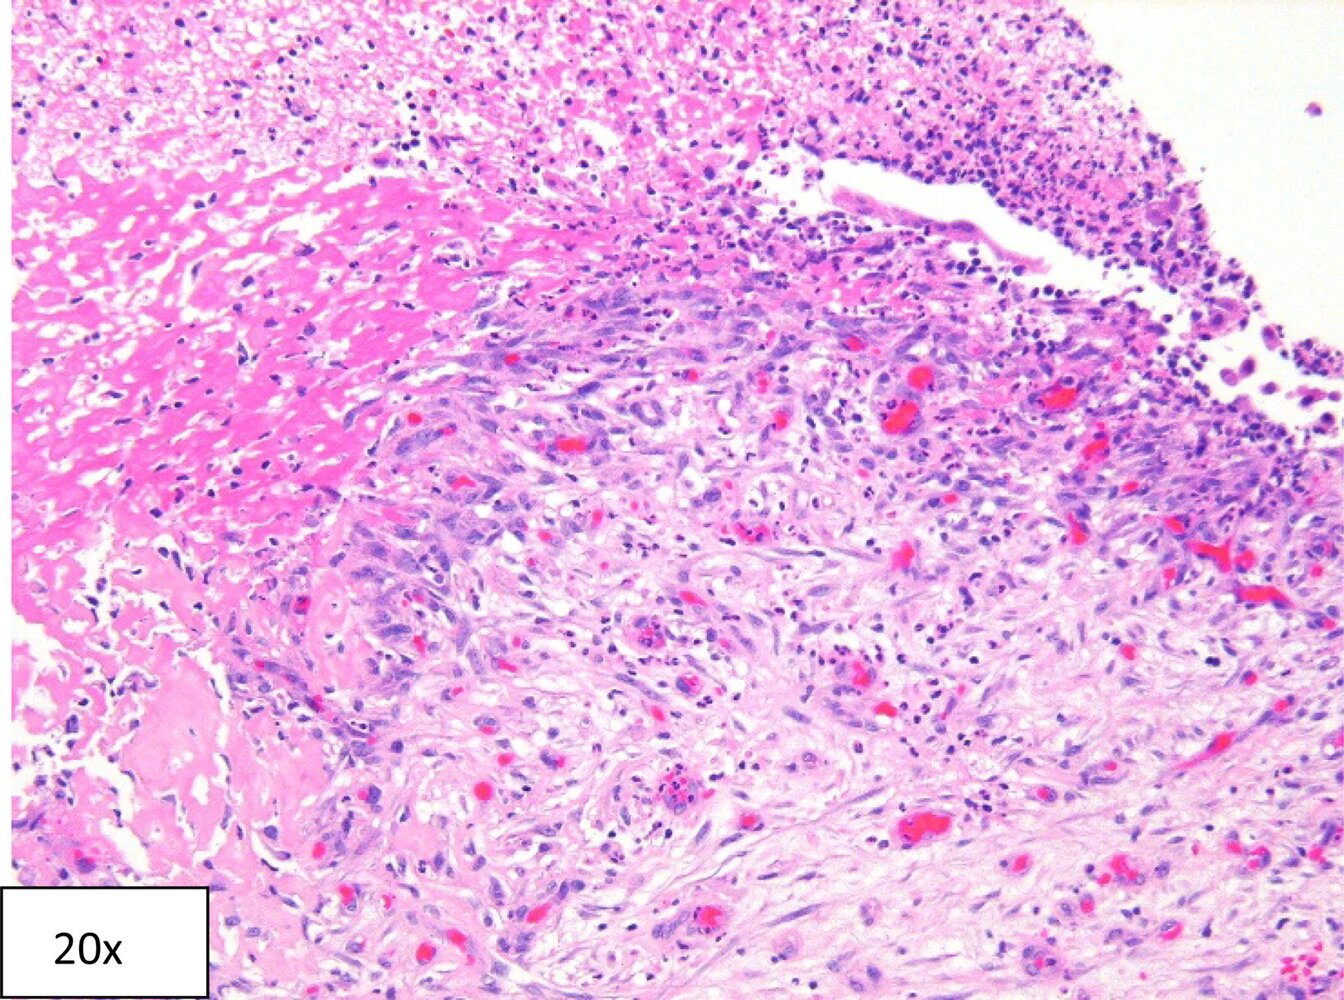

Renal biopsy [6][13]

• Indications include:

• No improvement or the patient worsens after 3–5 days of supportive care and withdrawal of potential causative agent.

• Guiding treatment of suspected causes

• Findings

• Diffuse or patchy peritubular inflammatory cell infiltrates: T-cell lymphocytes and monocytes (macrophages, eosinophils, and plasma cells)

• Interstitial edema

• Sparing of glomeruli and vessels

• Renal biopsy [6][9]

• Can be used to diagnose specific causes that would alter management or help determine the prognosis

• Findings include tubulointerstitial fibrosis and tubular atrophy.